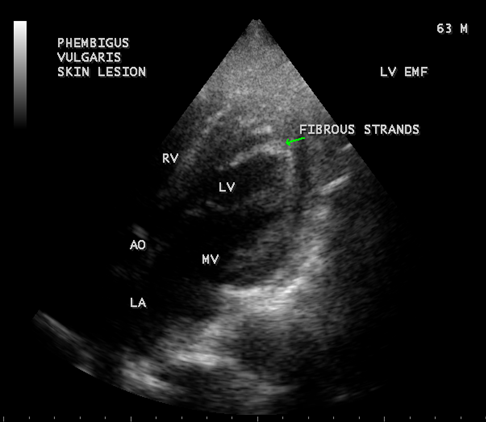

Figure 39: Left ventricular endomyocardial fibrosis in Pemphigus skin lesions in a 63-year old male.

A left ventricular EMF mimicking apical left ventricular hypertrophic cardiomyopathy in a year-old boy as shown in Figures 23, 24 and 25 in a 2-year old male child and an apical right ventricular cardiomyopathy in a year-old female as shown in Figure 26 mimicking as right ventricular EMF have been found by Transthoracic echocardiographic screening. A right ventricular EMF associated with Psoriasis as shown in Figure 3 to7 in a 52- year old male and a left ventricular EMF associated with pemphigus in a 63- year old male as in Figure 39 were detected in this region of Thoothukudi.